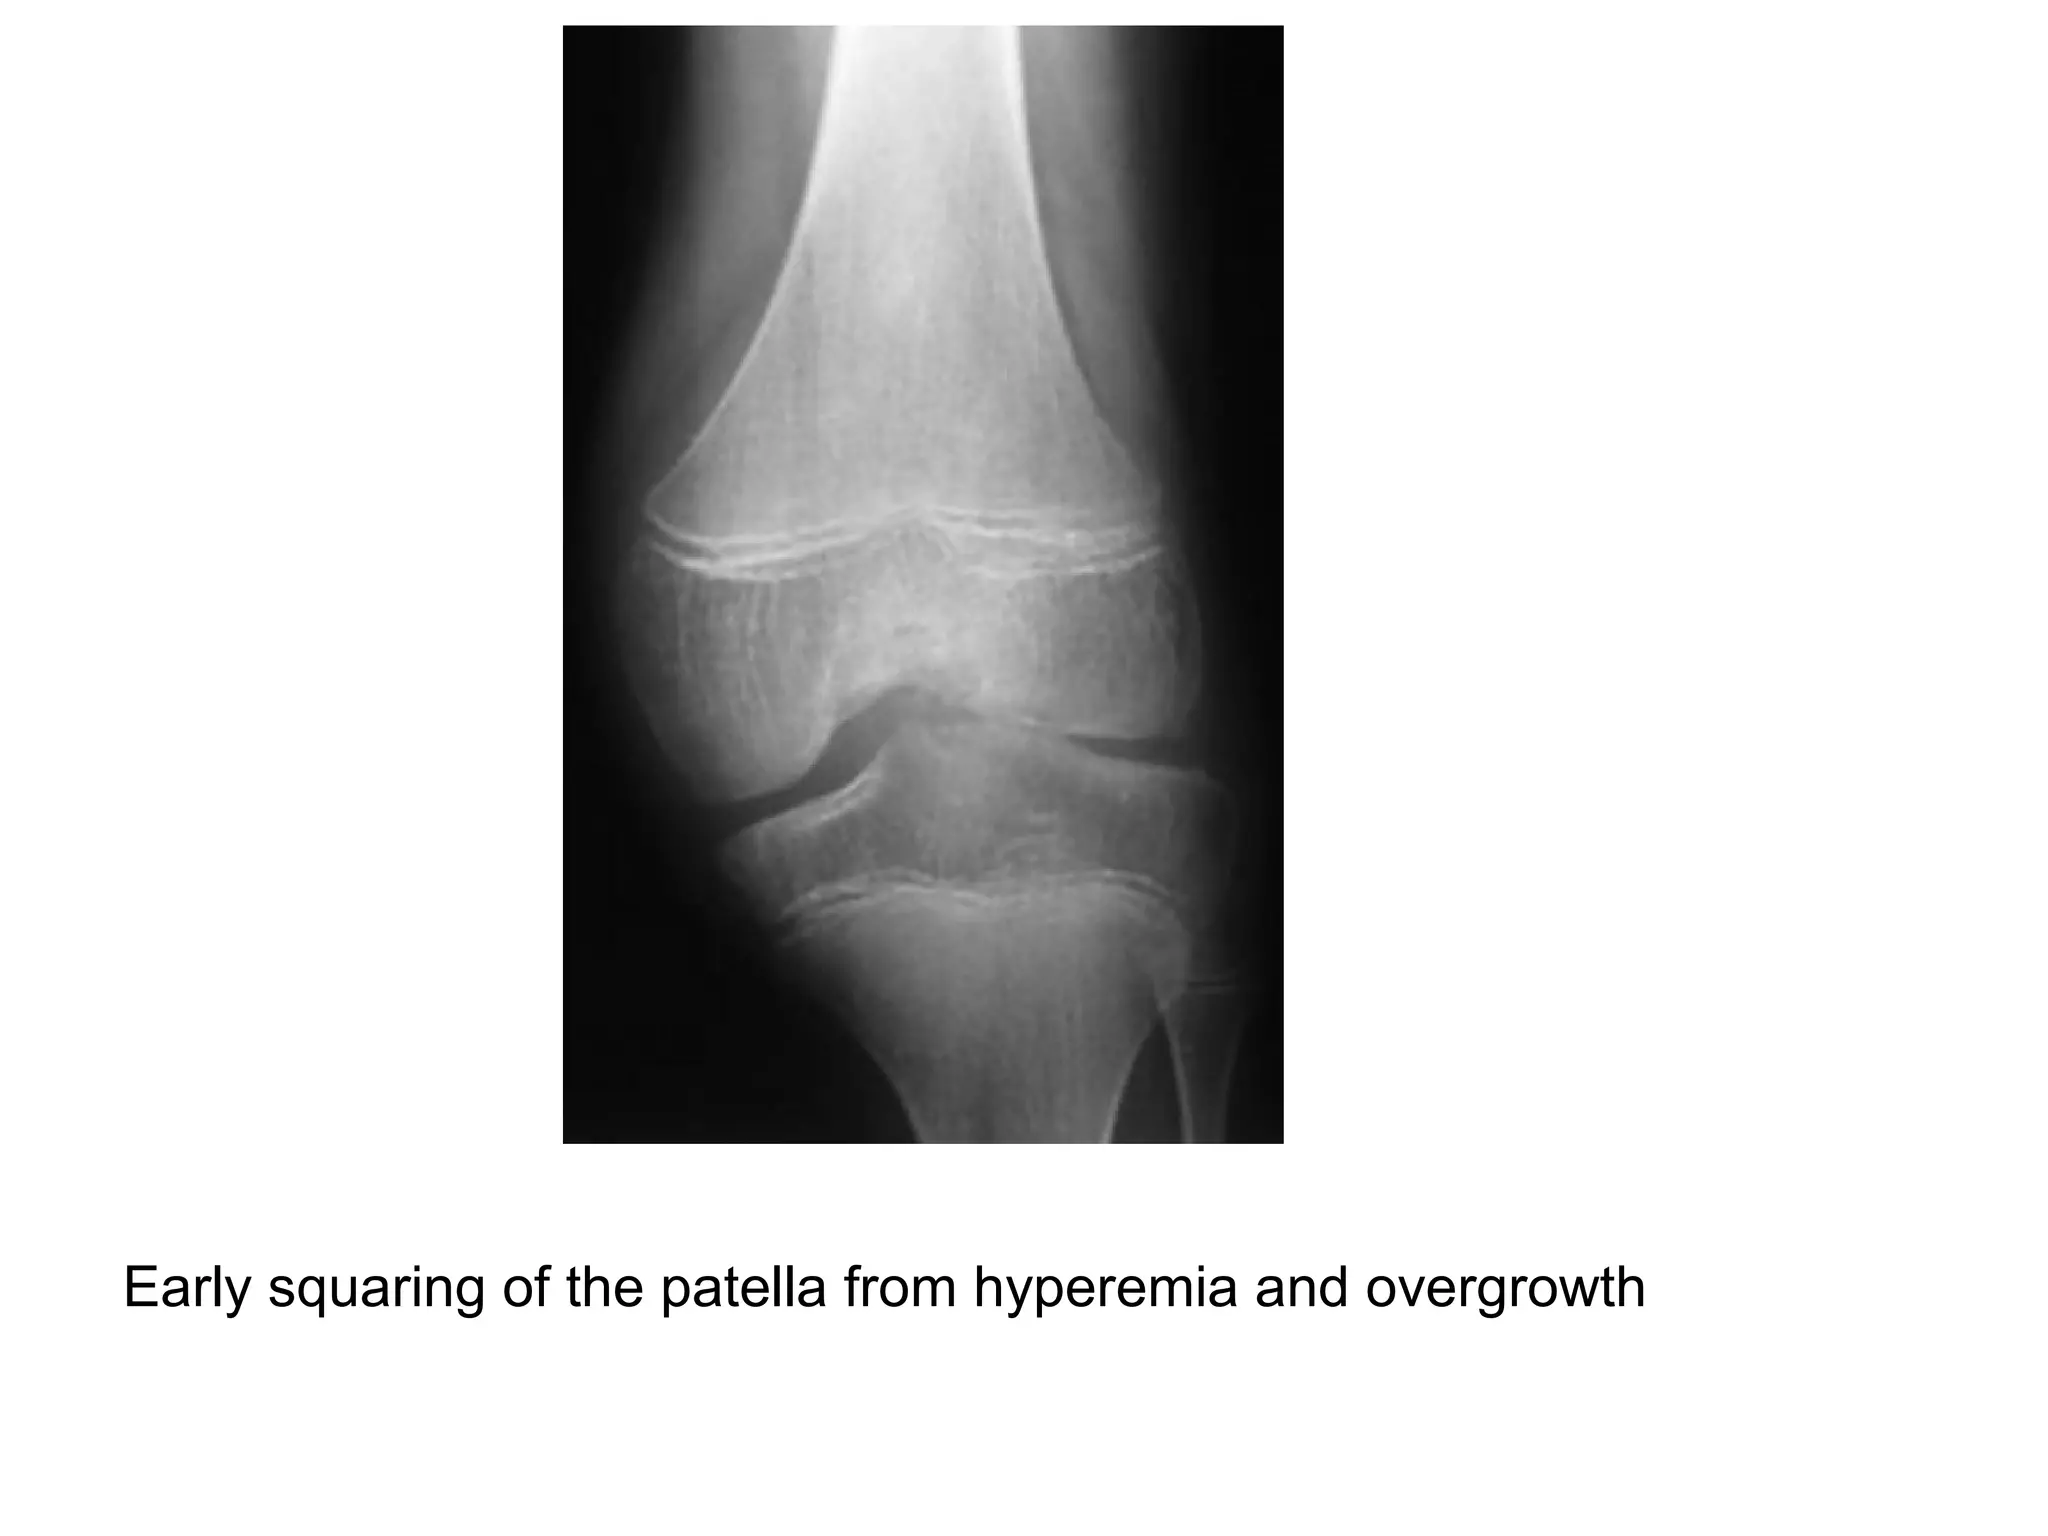

*Stage III : early subchondral bone cysts , squaring of the

patella , widened notch of the distal femur or humerus &

Grade III , early narrowing of the joint space from loss of cartilage and

spur formation on the margins of the condyles , the patella

demonstrates early squaring from hyperemia and overgrowth

Early squaring of the patella from hyperemia and overgrowth